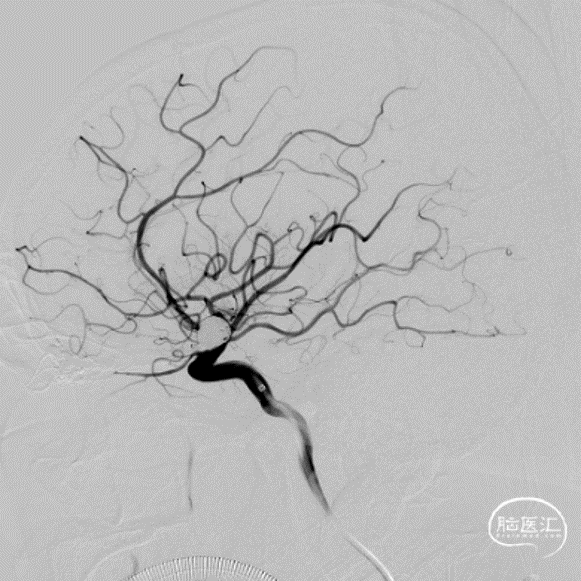

治疗经过

二期治疗